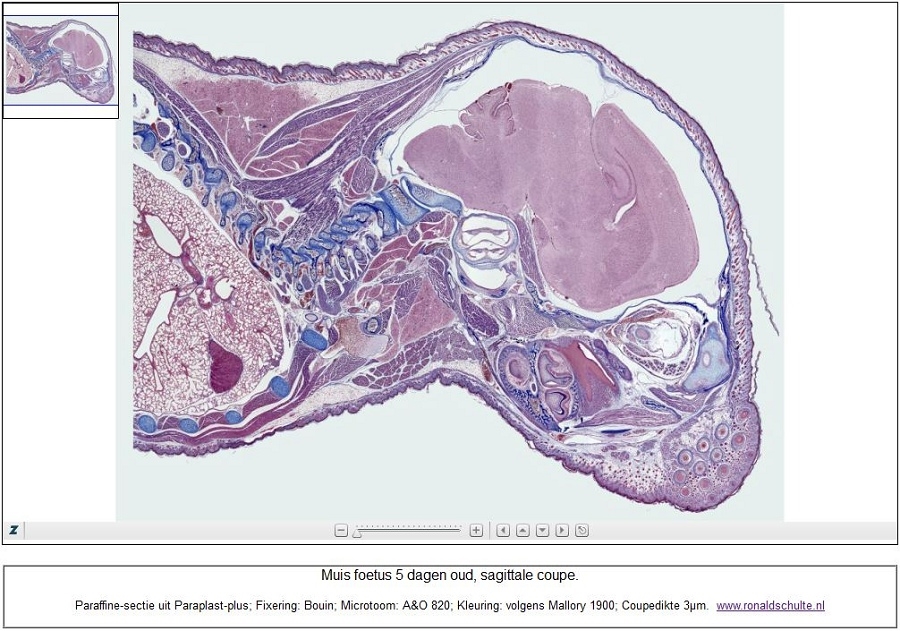

Wer mal sehen möchte wie das Innenohr, Zahnbildung, Gehirn, Speicheldrüsen, Hippocampus, Wirbel mit viele Nerven usw aussieht kann mit diesen Link das zoomify Bild abrufen und eine Reise durch den Kopf machen. Auch die Schnurrhaare sind hier rechts unten zu finden.

Maus ist fünf Tagen alt, Fixiert in Bouin und eingebettet in Paraplast Plus.

Bild ist ein Stitch von 281 Einzelbilder, Objektiv Leitz Plan Fluotar 10x.

Eine frage bleibt noch, wer hat den Antwort: "zwischen das Gehirn und Gaumenbein ist ein sagittal angeschnittene grosse Nerv zu sehen. Könnte das den Sehnerv sein?"